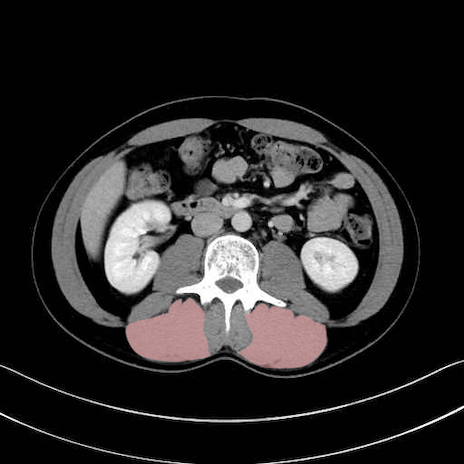

脊柱起立筋(erector spinae)のCT画像の解剖

脊柱起立筋 (Erector spinae)

多裂筋 (Multifidus)